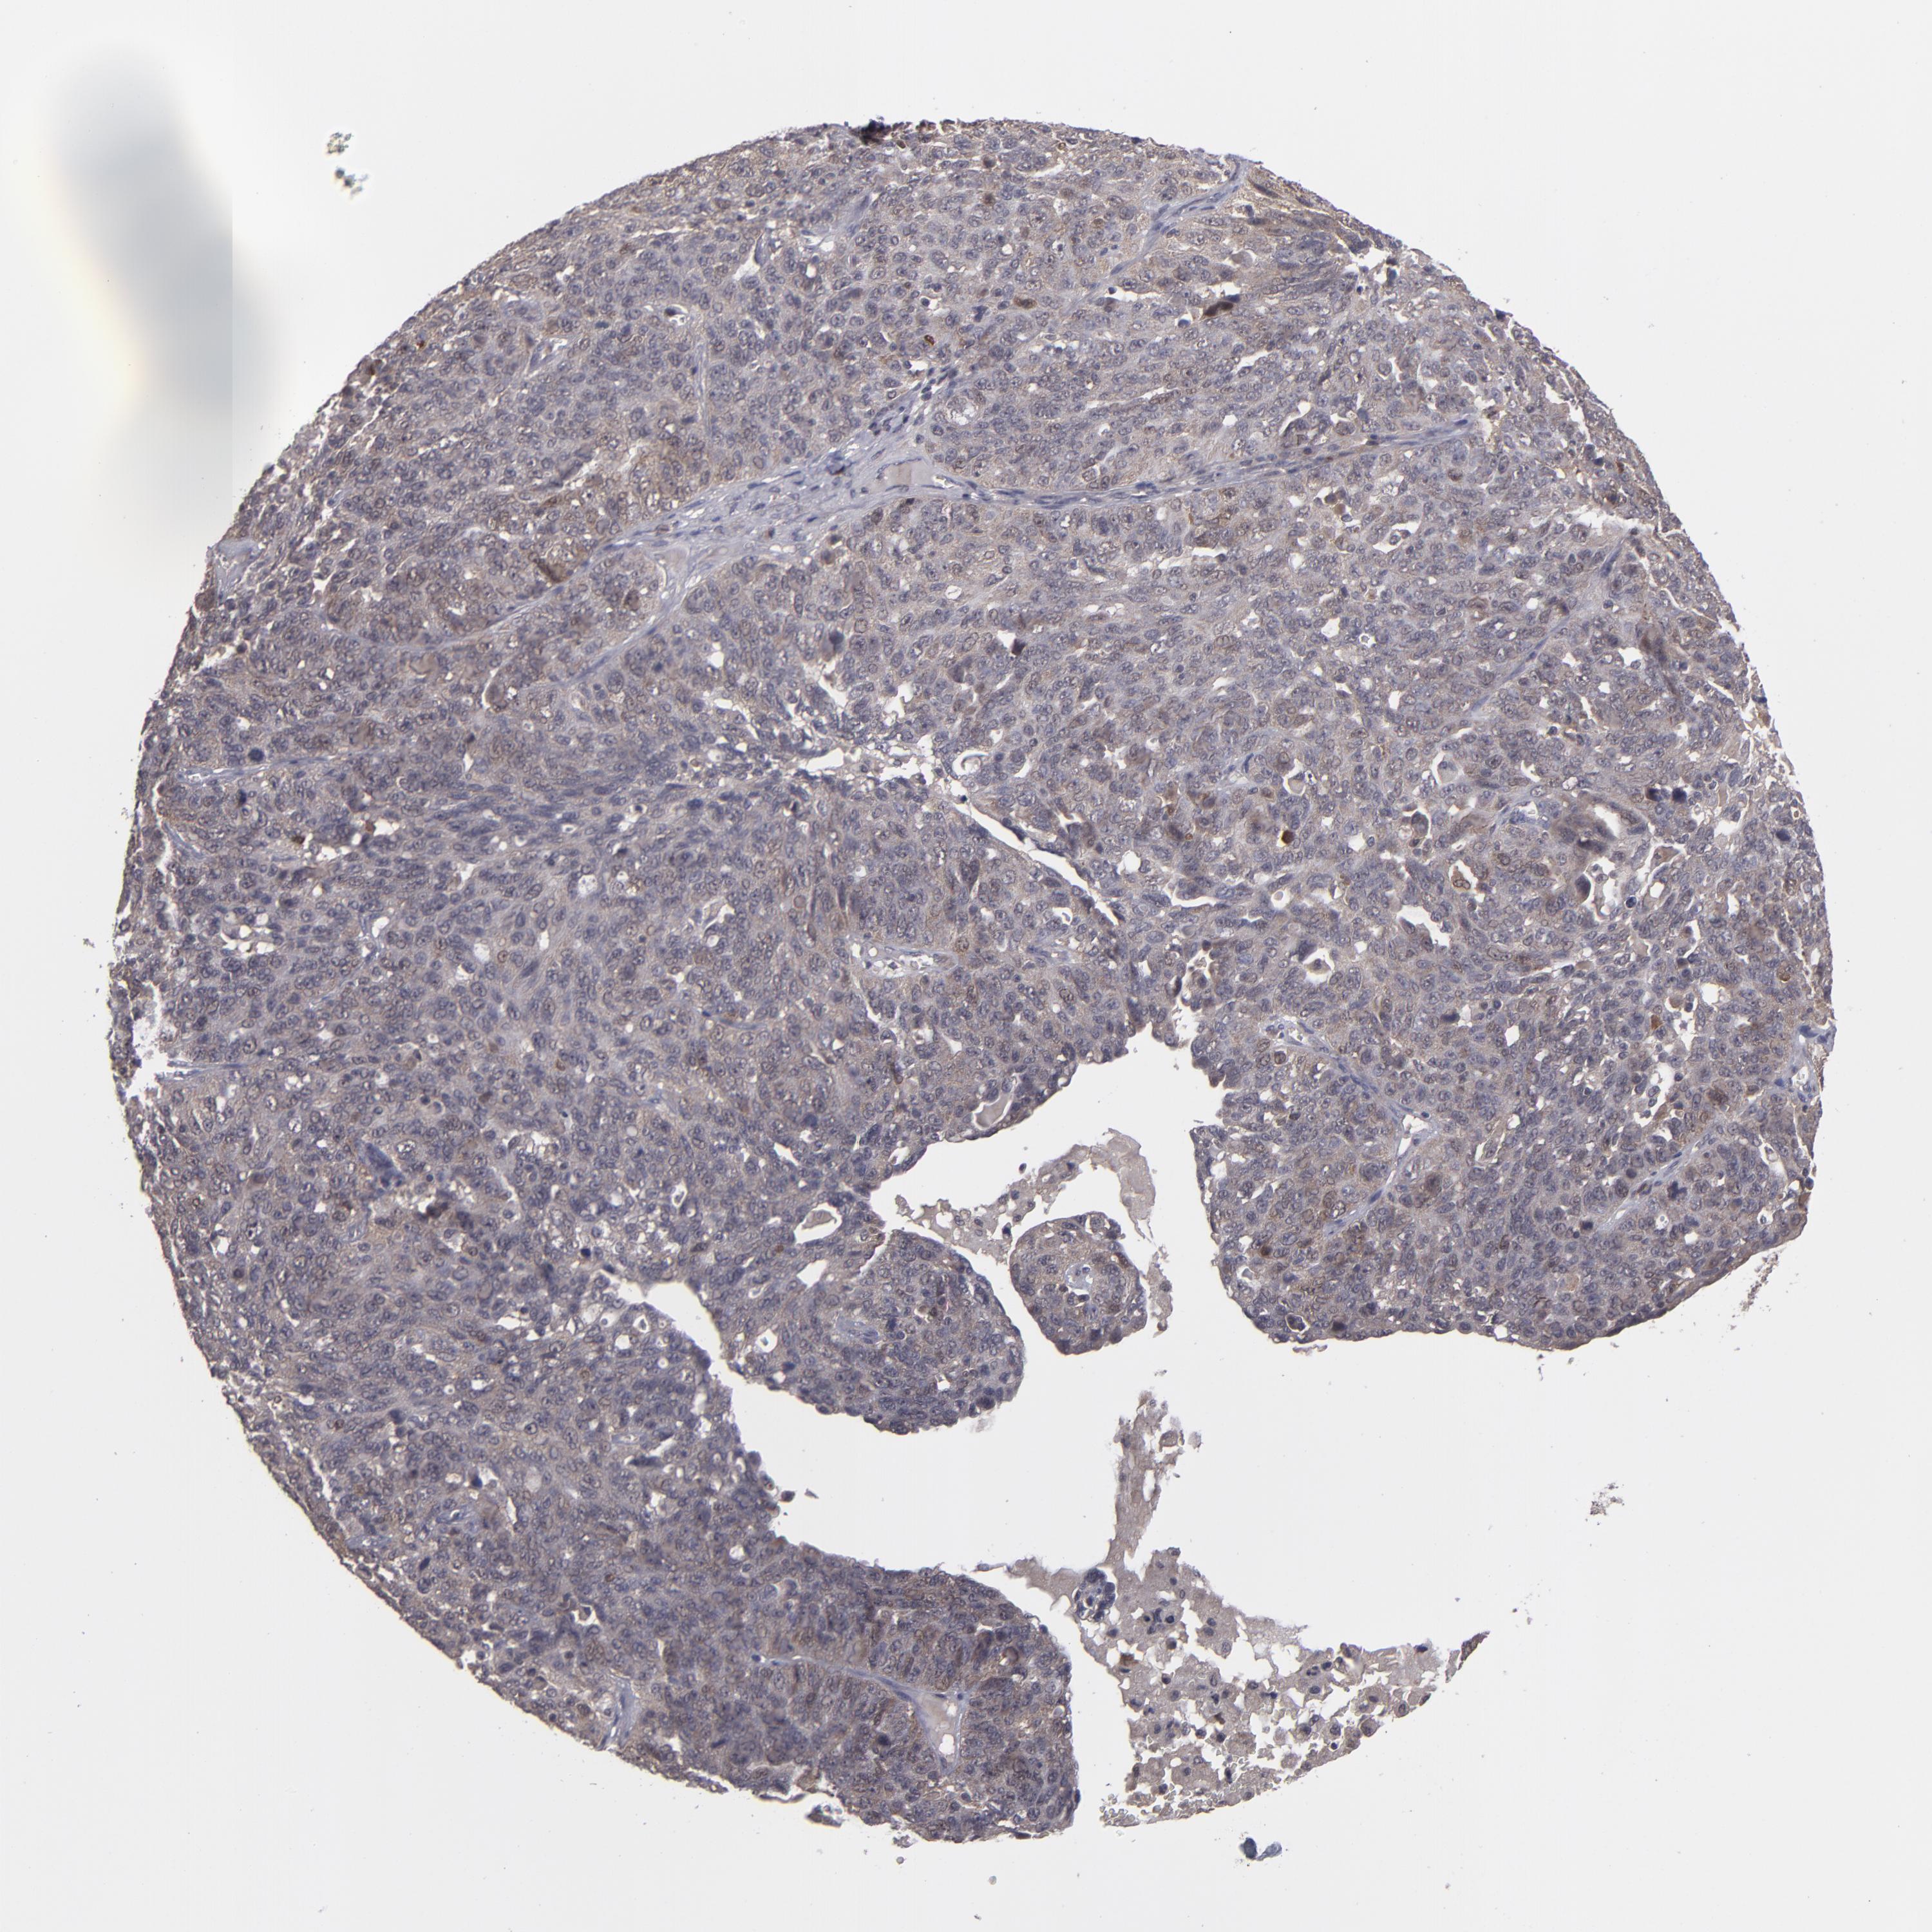

OVARIAN CANCER - Protein expressioni

A mouse-over function shows sample information and annotation data. Click on an image to view it in a full screen mode. Samples can be filtered based on level of antibody staining by selecting one or several of the following categories: high, medium, low and not detected. The assay and annotation is described here.

Note that samples used for immunohistochemistry by the Human Protein Atlas do not correspond to samples in the TCGA dataset.

Antibody stainingi

Antibody staining in the annotated cell types in the current human tissue is reported as not detected, low, medium, or high, based on conventional immunohistochemistry profiling in selected tissues. This score is based on the combination of the staining intensity and fraction of stained cells.

Each image is clickable and will lead to virtual microscopy that enables deeper exploration of all samples and also displays staining intensity scores, fraction scores and subcellular localization as well as patient and tissue information for each sample.

Antibody HPA074922

Antibody CAB002784

Cystadenocarcinoma, serous, NOS